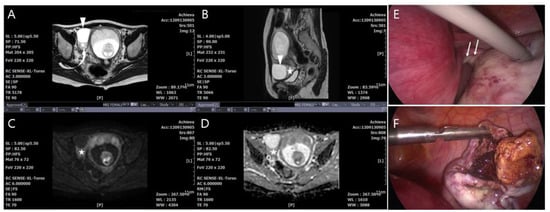

4.5. MRI Findings by a Multiparameter Imaging